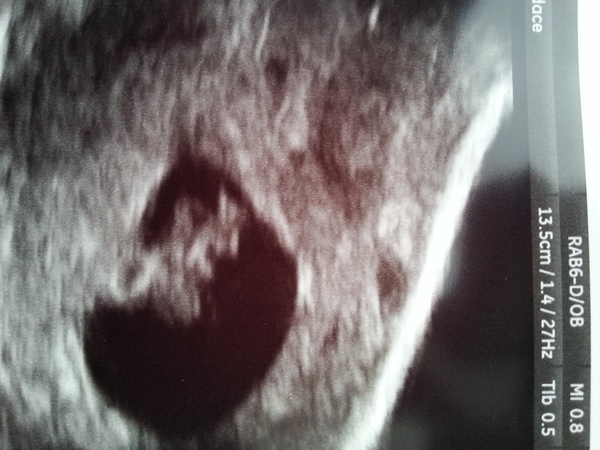

Little squidgelet. I do have a subchorionic haemotoma but it's less than a cm round so unlikely to cause any problems

notoast that scan looks fab! Love the name squidelet :-)